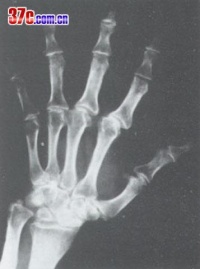

本病是在骨发育过程中发生的全身性、多发灶性、软骨坏死性疾病,造成的骨关节损害将持续终身,X

线征象归纳如下:

1.干骺端边缘模糊或凹凸不平,呈波浪状以至锯齿状。如病变继续发展,指骨端不整齐的边缘可呈碎裂现象。此时,关节无明显变形。

2.以骨骺与骨干开始融合为特征。骨骺自中央部分开始融合,渐扩展到边缘,骨骺本身亦有破坏、分节、不整等现象,也可能完全被吸收。干骺端可呈杯口状凹陷,骨髓嵌入其中而早期愈合,停止发育。

3.干骺完全融合,骨的纵向发育停止,病骨变短变粗。因为各干骺的融合迟早不同,以致各指骨可呈现长短不齐,骨端宽大变形,使关节粗大。

由于病人发病年龄、受累部位、病变发展阶段不同,X线有不同表现。原苏联与国学者曾主要依据于部X线改变将本病分为以下几型。

⑴、干骼型:以干骼端改变为主,包括临时钙化带变薄、模糊、中断、消失,干骼端出现凹陷、硬化等。干骺型发生于学龄前及学龄儿童,反映骺板软骨坏死后的继发变化,代表大骨节病较早的损害,临床症状多为阴性或非常轻微。干骺型的X线变化除很明显的硬化在非病区儿童中较少见外,其他征象均可在非病区儿童中出现。因而在同一地区没有发现Ⅰ度以上典型病例的情况下,不宜仅凭某几点干骺端X线改变就诊断为本病。前面谈过的日本发现的所谓大骨节病,就是由于没有充分注意到这一点。⑵、干骺骨骺型:除上述干骼端变化外,骨骺也有变化,如骨骺常呈锥状或其他变形,嵌入凹陷的干骺端等。此型多发生于学龄及青春期,反映骺板软骨的一部分发生全层坏死,其干骺侧和骺核侧同时有生长障碍和骨质变化,局部骺板早期穿通化骨。这是干骺型的进一步发展。

⑶、骨端型:以骨端改变为主,包括骨性关节面模糊不整、变薄、中断、凹陷变形、硬化、甚至碎裂等改变。多发生于学龄儿童至青春期以后年龄段,反映关节软骨深层坏死继发的骨质改变。骨端的变化发展较慢,合并其他关节损害多。骨端出现变化的诊断意义比干骺端的变化更重要,更具有特异性。

⑷、骨关节型:见于骺线闭合、骺板软骨消失之后,包括骨关节面的严重破坏、凹凸不平、增生硬化、骨刺形成、骨质碎裂、囊性变、骨端粗大畸形等改变。常累及多关节,X线所见类似退行性(增生性)关节病,是本病的晚期表现。